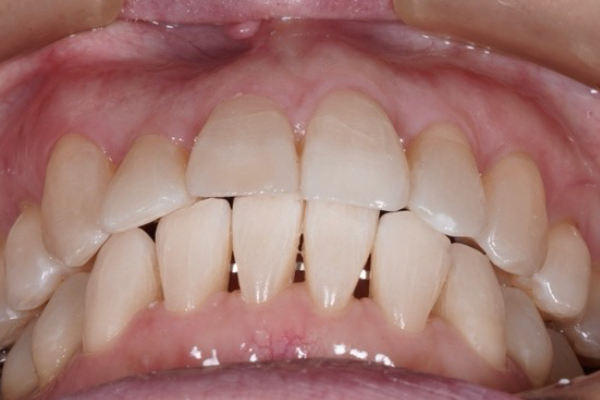

矯正治療前

50代女性のAさん(札幌市在住)

犬歯は外側にあり八重歯になっていました。ずっと歯並びは気になっていましたがなかなか機会がなく矯正治療はできませんでした。

前歯で物を咬めなく、下顎の状態が不安定でどこで咬んでいいかわからないことも悩みでした。

40代くらいから歯のトラブルが増えこのままでは歯がなくなってしまうと思い矯正治療をする決断をしました。